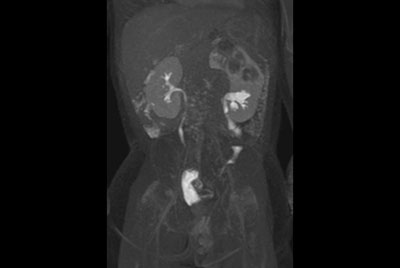

Pediatric Urography